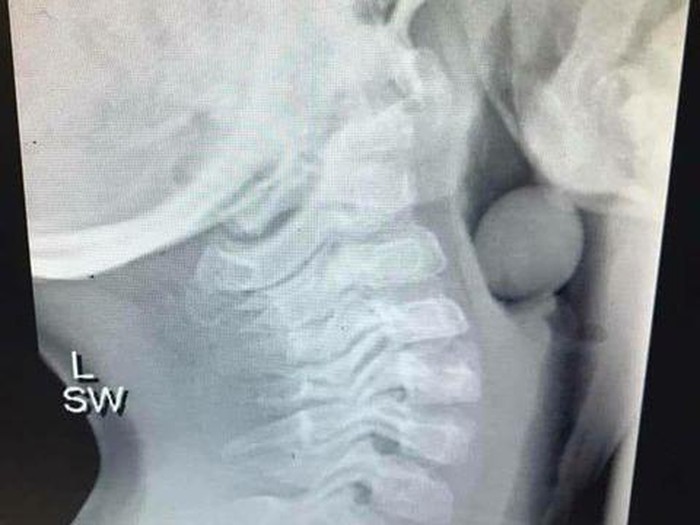

Petugas kesehatan mental sekaligus blogger Angela Henderson mengupload foto x-ray di halaman Facebook-nya 'Finlee and Me' setelah mendapat persetujuan dari orang tua sang anak. Dalam tulisannya Angela mengatakan sang anak perlu dioperasi untuk mengeluarkan buah anggur.

"Dia sangat beruntung karena sebagian saluran udaranya masih terbuka karena kalau tidak ini akan berakhir dengan sangat buruk," lanjut Angela.

Foto: Facebook / Finlee and Me |

Foto: Facebook / Finlee and Me